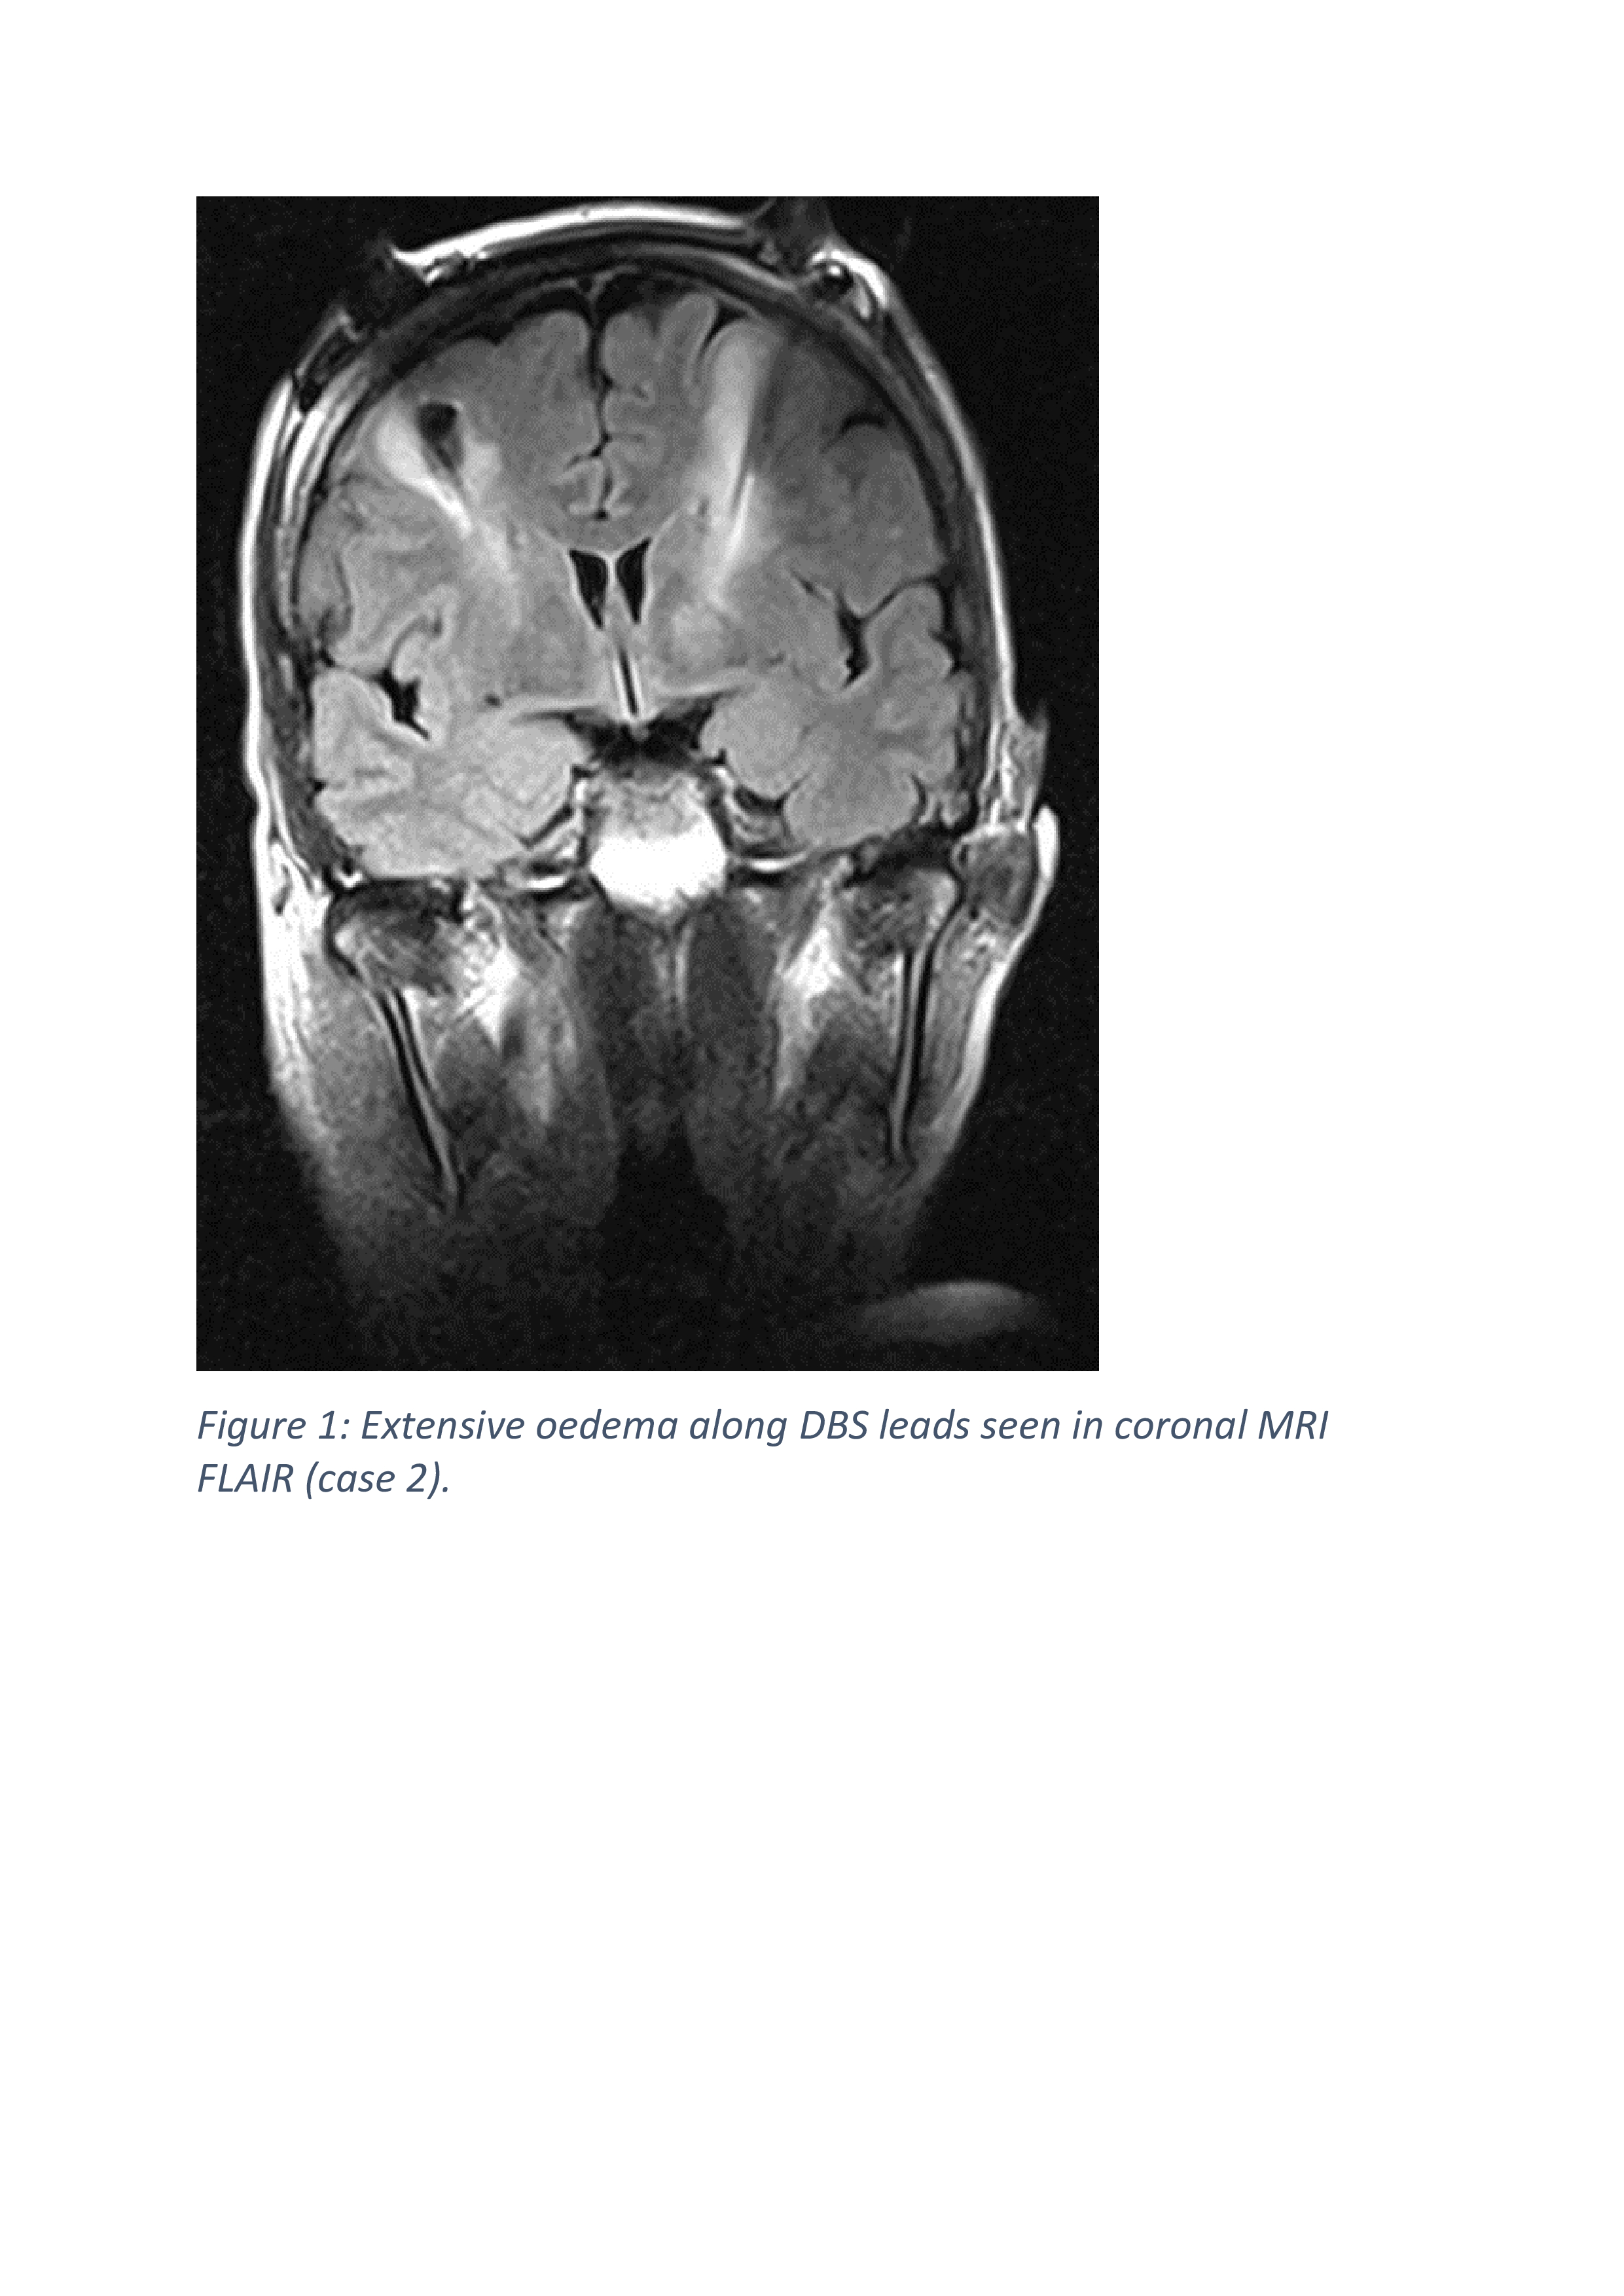

Results: The age at presentation was 62, 63 and 74 years old for case 1, 2 and 3. All the patients were female. The duration of Parkinson’s disease prior to surgery was 14 years, 15 years and 8 years respectively. All patients developed symptoms (confusion, disorientation and seizure) after 24 hours post-operation. There was no fever. Investigations performed did not support infections. EEG performed on all the cases showed asymmetric rhythmic slowing with embedded sharp waves with evolution over anterior head region. The MRI brain imaging detected bilateral asymmetrical peri-lead oedema. Despite treatment with anti-seizure and corticosteroid, patients remain encephalopathic. After clinical consideration, decision was made to remove the DBS implants at day 63, 4 and 9 post-operatives respectively. Brain biopsy results from case 2 revealed features consistent with mild acute encephalitis, however, in case 3; it showed ischaemic, reactive changes with no specific inflammatory process. CSF PCR from case 2 indicated Lactococcus lactis 16s rDNA detected, therefore, she received a 4 weeks course of antibiotics. Investigations for porphyria was performed in view of strong family history however; the result was negative. Follow up EEG showed resolution of epileptiform activity. All patients improved soon after and underwent rehabilitation.

Figure 1